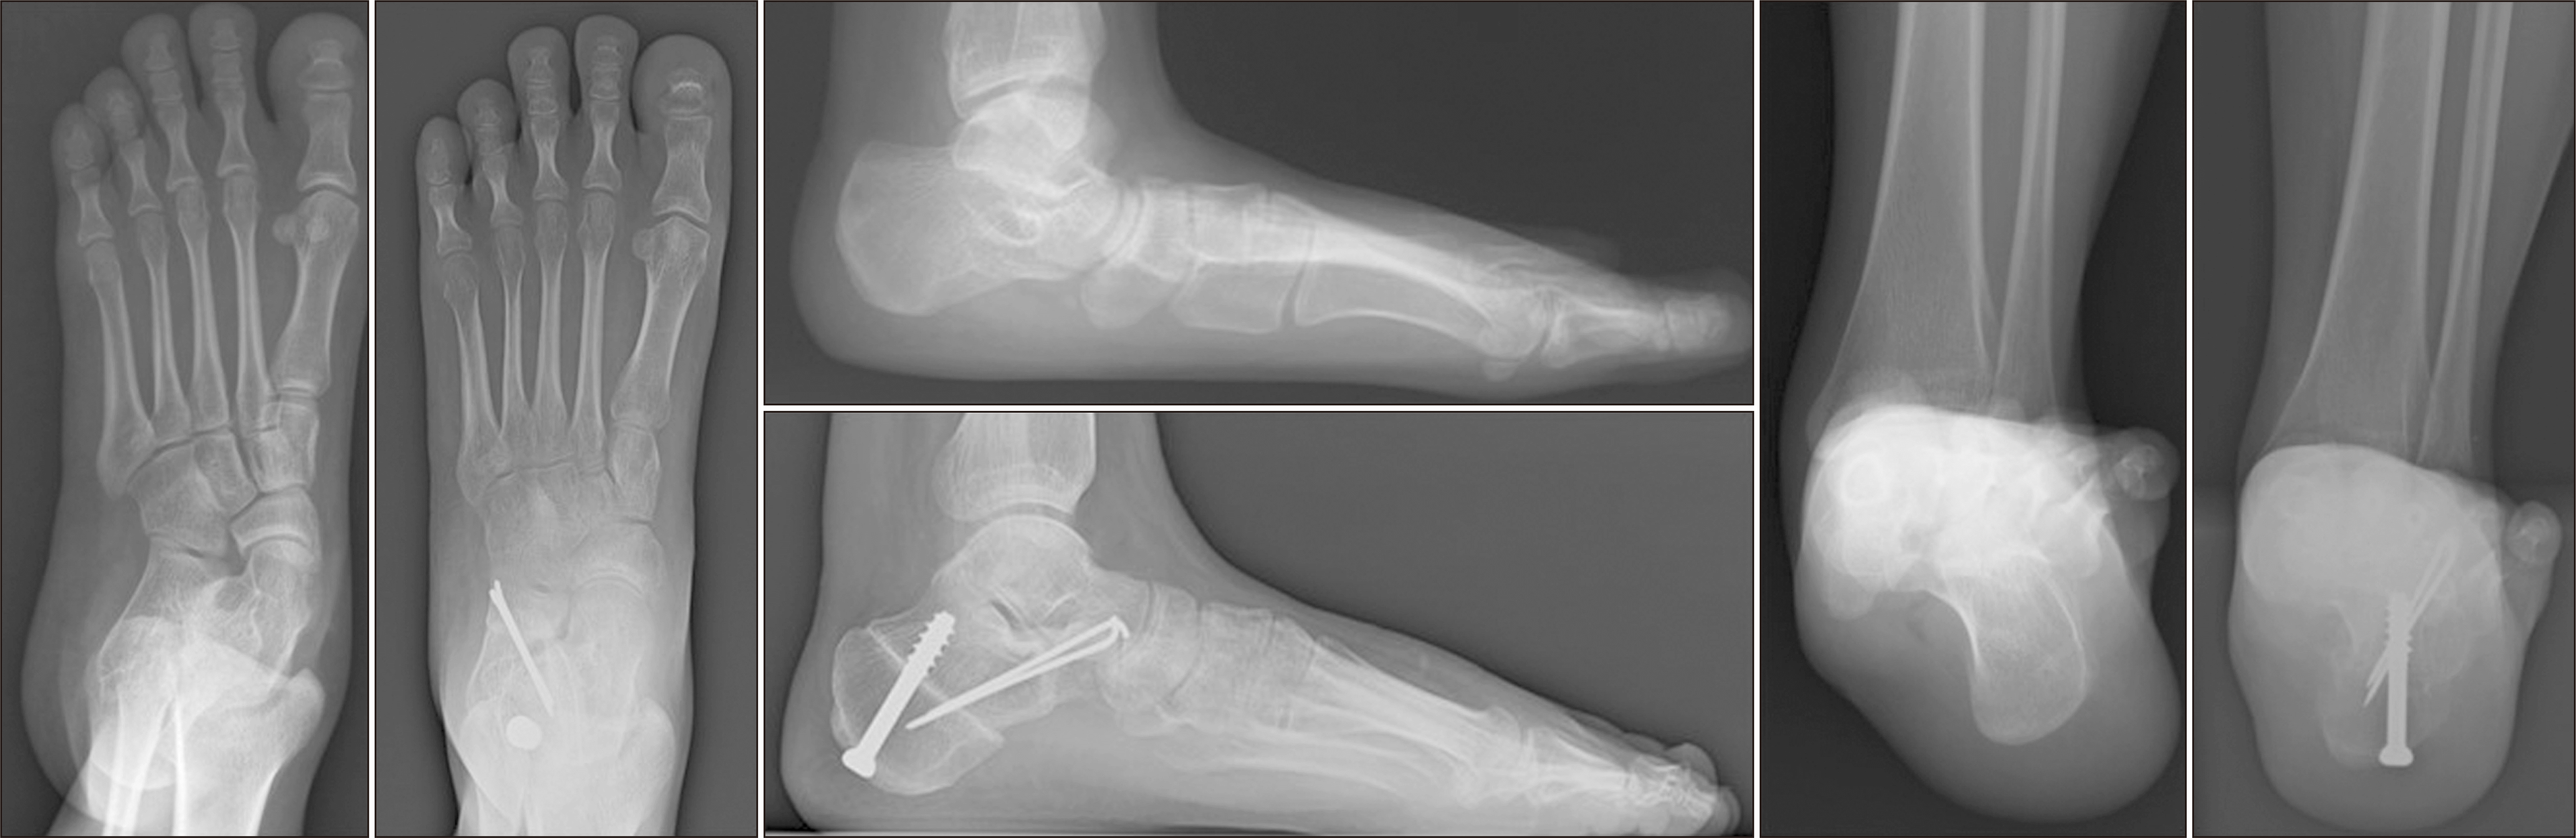

체중부하 방사선 촬영은 편평족의 진단에 있어 가장 표준이 되는 검사로, 체중부하 족부 전후면, 족부 측면, 족관절의 전후면 혹은 모티스 영상(mortise view) 및 후족부 정렬 촬영(hindfoot alignment view)8) 등이 진단을 위해 권고된다.9) 족부 전후면 사진에서는 전족부 혹은 중족부의 외전 정도를 평가할 수 있으며 거주상 관절 피복각(talonavicular coverage angle), 거주상 관절 이탈률(talonavicular uncoverage percent) 등 이를 반영하는 매우 다양한 지표를 측정할 수 있다(Fig. 1). 족부 측면 사진에서는 내측 세로궁의 소실 정도를 평가할 수 있는데, 흔히 쓰이는 지표로는 Meary angle이라 불리는 외측 거골-제 1중족골 각도를 측정할 수 있다(Fig. 2). 또한 족부의 내측주(medial column) 관절들의 족저부 벌어짐(plantar gapping) 정도를 확인하여 내측주 불안정성 정도를 평가할 수 있으며 족근동에서 거골과 종골의 직접적인 충돌 혹은 족근동 주변 골의 경화소견이나 낭종성 병변 등을 통해 족근동 충돌을 간접적으로 확인할 수 있다(Fig. 3). 족관절의 전후방 혹은 모티스 사진에서는 거골의 외반경사(valgus talar tilt)의 유무를 통해 족관절의 불안정성을 평가할 수 있으며 변형이 많이 진행한 경우 비골하 충돌 또한 확인할 수 있다(Fig. 4). 마지막으로, 후족부 정렬 촬영을 통해서는 후족부 외반 변형의 정도를 평가할 수 있는데, 주로 후족부 정렬각(hindfoot alignment angle) 혹은 후족부 모멘트암(hindfoot moment arm)을 측정한다(Fig. 5).10)

새로운 분류체계는 변형의 종류와 위치에 따라 A~E로 나누고, 각 변형의 유연성 유무에 따라 1기 유연성 변형과 2기 강직성 변형으로 분류하였다(Table 2).6) 이러한 변형은 진찰 소견과 체중부하 단순 방사선 촬영을 통해 평가하도록 하였고, 체중부하 전산화 단층촬영의 경우 아직 전세계적으로 사용되고 있지는 않기 때문에 판단기준에서 제외되었다. A형 변형은 후족부 외반 변형으로 후족부가 신체의 정중선으로부터 외측으로 전위된 변형을 뜻한다. 임상적으로 진찰 시 후족부 외반이 관찰되거나, 후족부 정렬 영상에서 후족부 정렬각 혹은 후족부 모멘트암의 증가 등으로 판단할 수 있다(Fig. 5). B형 변형은 전족부 혹은 중족부의 외전 변형으로 전족부나 중족부가 후족부를 기준으로 외측으로 전위된 변형이다. 체중부하 족부 전후면 사진상 거골두에 대한 주상골의 피복(coverage) 정도가 감소하고, 거주상 관절 피복각이 증가한다(Fig. 1). 또한 이 변형에 의해 족근동 충돌이 발생할 수 있으며, 족근동 주변의 압통 및 통증이 발생할 수 있다. 체중부하 족부 측면사진상 족근동에서 거골과 종골의 직접적인 충돌 소견이 보이거나, 족근동 주변의 거골과 종골의 골경화 혹은 골낭종 등을 통해 간접적으로 확인할 수 있다(Fig. 3). C형 변형은 전족부의 내반 변형 혹은 내측주 불안정성으로 임상적으로 후족부를 중립 위치에 고정한 뒤 관찰하였을 때 전족부가 내반을 보이는 변형이다(Fig. 8). 일부에서는 이를 회외 변형으로 불러야 한다는 의견도 있으나 현재 혼용해서 쓰이고 있다.11,20) 내측주 불안정성은 체중부하 족부 측면사진상 거주상 관절, 주상설상 관절(naviculocuneiform joint) 및 족근중족 관절(tarsometatarsal joint)이 배측 불안정증을 보이는 것으로, 영상검사상 족저부 벌어짐 유무 등을 통해 내측주 불안정성의 유무 및 위치를 확인할 수 있다(Fig. 3). D형 변형은 거근관절의 탈구 혹은 아탈구 변형으로 거골이 종골을 기준으로 내회전, 족저굴곡되면서 종골은 거골을 기준으로 외회전, 외반, 외측 전위가 발생하면서 거골하 관절의 아탈구가 발생하고, 심한 경우 비골하 충돌을 일으키게 된다(Fig. 4). E형 변형은 발목관절의 외반 변형이 발생한 경우이며, 족관절의 전후방 혹은 모티스 사진에서 거골의 외반경사로 확인할 수 있다(Fig. 4). 이 분류의 적용은 한 환자에 대해 A 부터 E까지의 변형 유무를 확인하고, 각각의 변형이 유연성 변형인지, 강직성 변형인지에 따라 1기와 2기를 나누는 방식으로 적용한다.

앞서 기술한 두 수술법인 내측 전위 종골 절골술과 외측주 연장술은 단독으로 시행하기도 하지만, 다른 수술법과 함께 시행하는 경우도 많다. 특히, 내측 전위 종골 절골술은 후족부 외반을 교정하며 외측주 연장술은 전족부 외전 및 내측 새로궁을 교정하기 때문에 함께 시행하였을 때 서로 보완적인 효과를 보여 평발의 3차원적인 변형을 교정하는 데 유용하다.51-54) Zanolli 등55)은 카데바 실험에서 이중 종골 절골술이 내측 전위 절골술 단독에 비해 보다 나은 교정력 및 반복된 부하에 대한 유지력을 보였다고 보고하였으며 Smith 등34)이 시행한 전산화된 모델시험에서 두 절골술을 함께 시행하였을 때 단독 수술에 비해 변형을 더 잘 교정할 수 있다는 결과를 얻었다. 따라서 전족부 외전과 후족부 외반이 동반된 경우 이중 종골 절골술을 통한 교정을 고려할 수 있다(Fig. 11).51)

Figure 11

Preoperative and postoperative plain radiograph of the weight bearing foot anteroposterior, lateral, and hindfoot views of a 20-year-old female patient with a unilateral flatfoot deformity who was performed double calcaneal osteotomy.